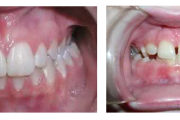

Ravijärgne seis. Jäävhammas on täielikult lõikunud.

) Röntgenülesvõte. Ülemise esimese jäävmolaari lõikumine on takistatud 2. piimamolaari tõttu

Esimese jäävmolaari ektoopiline lõikumine